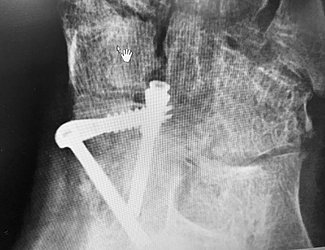

The surgery may involve the removal of the damaged joint and the permanent stiffening of the bones via plates fixed by screws to facilitate bone fusion as healing occurs. Talonavicular fusions a re done for two main reasons:

It fuses together two bones, the. The talus and navicular bones are then bolted together typically with screws and hardware (2). I am no longer on pain meds including anti inflamitories i still have inflammation but i expect by one year that will no longer b an issue.

After the fusion there is less movement of the foot. Two foot bones (talus and navicular or talus and calcaneous) are fused together and screws or staples are inserted to maintain the position. This in turn can cause inflammation, pain, and joint deformity.

Because of that my surgeon used only two small staples to hold my two bones in place. Arthritis of the joints, because of a previous injury that has damaged the joints, a generalised condition such as osteoarthritis or rheumatoid arthritis, or because the joint is just wearing out for some other reason My cast was changed at 2 weeks & will b changed at 5 weeks.